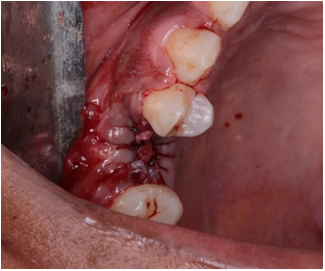

Patient E.L.S, 31 years old, female, leucoderma, compared to the outpatient clinic of oral rehabilitation clinic at the Regional University Center of Brazil - UNIRB, without dental course, complaining of “broken tooth”. After anamnesis analysis it was found that one patient did not present any systemic alteration. He was then classified as an ASA 1 patient with good oral health. On radiographic examination, a residual root was found in unit 15 (Figure 1), indicating an extraction of the unit. It was proposed as treatment plan the rehabilitation of the unit with bone implants performed in two surgical times and filled with socket with equine graft, opting for the biomaterial Bio-Gen - Bioteck®.

Figure 1 (A) Initial clinical aspect. (B) Initial radiographic appearance.

For extraction of the started unit, anesthesia with Lidocaine HCL 2% + epinephrine 1: 100,000 were performed. Thus, infraorbital nerve block and papillary complementation were performed. Then, an intrasucular incision (selected 15C) was made, followed by detachment of the gingival tissue with the Molt No. 9 detacher (Figure 2). Immediately after detachment, initiate the procedure of periodontal ligament dislocation (LP) and disconnection of the root remnant, due to the need for minimal trauma for the conservation of the alveolar walls, try an atraumatic extraction of the units using the straight chelate period ®(Figure 3). Next, the alveolus was curettable with Lucas's curette associated with abundant irrigation with saline for cleaning the alveolus.

Figure 2 Appearance after tissue detachment.

Figure 3 Dislocation and extraction of the periotome unit.